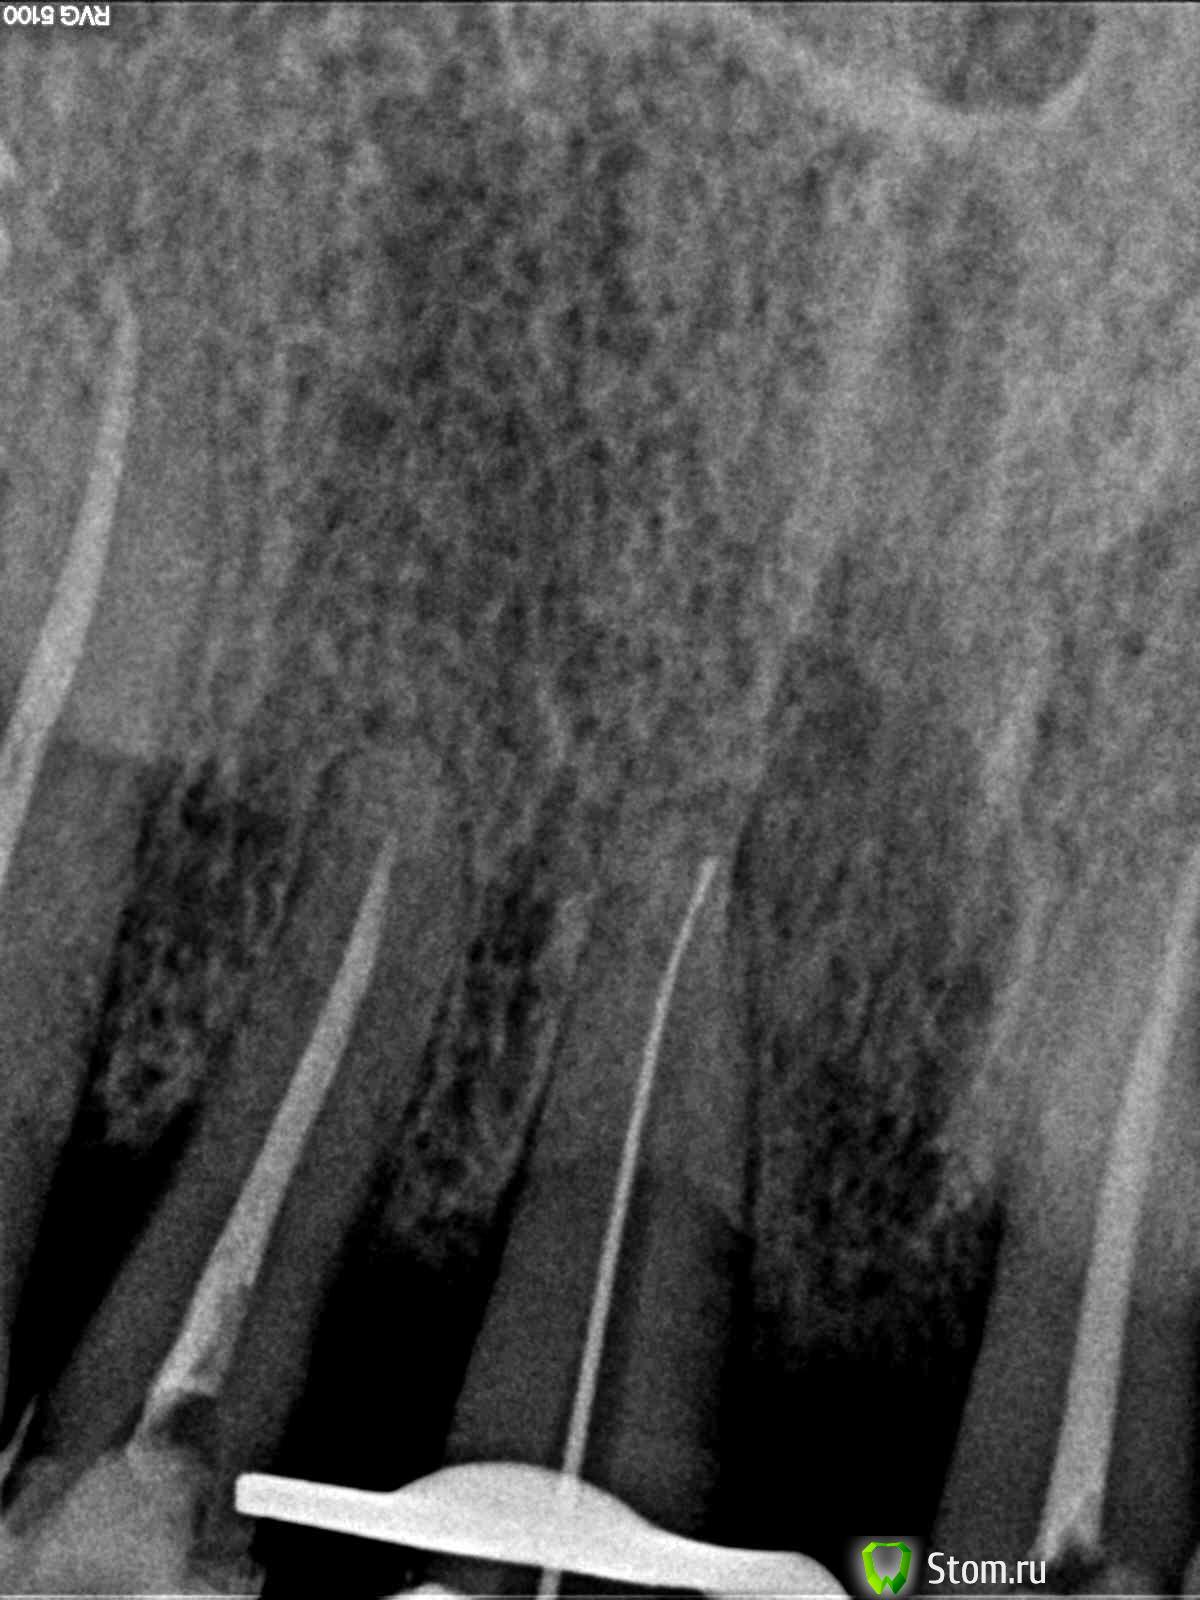

Magdalena Опубликовано 31 января, 2012 Поделиться Опубликовано 31 января, 2012 (изменено) В одном из филиалов стоял микроскоп, случайно узнала, что никто им не работает, забрала себе.)На удаленных зубах потренироваться не успела - попались ситуации, когда скоп был нужен сразу в работе.1. Пациент 66 лет, перелечивание зуба 1.1 под коронку. По КТ - канал запломбирован чуть более 1\2 длины, на верхушке корня очаг разрежения костной ткани с нечеткими границами (КТ фоткала с экрана компьютера, не смогла скопировать ) В первое посещение - распломбировала канал на проходимую длину (в канале гутта), инструмент дальше не идет абсолютно, по КТ хода канала после пломбировочного материала не увидела.Оставила в канале раствор ЭДТА на неделю, пломба Витремер.Во второе посещение еще раз смотрю КТ - смущает меня все-таки такое разрежение, вроде тоооненько прослеживается ход канала. Все отмыла, привезла скоп - на "дне" канала увидела белую точку. Т.к. опыта лечения под микроскопом у меня не было - подумала что это блик, посмотрела под разными увеличениями - все-равно есть, решила пройти по точке УЗ - и сразу же провалилась ( и сердце упало тоже ) Канал при первичном эндо был заступенен.Пломбирование 2. Пациент 35 лет, перелечивание зуба 1.4 под коронку. КТ : каналы запломбированы на 1\2, расширение периодонтальной щели в обл. верхушек корней.щечный каналнебный каналСняла пломбу - в каналах - фосфат-цемент. Сразу привезла микроскоп, распломбировывала УЗ под контролем скопа.Снимок с файлами скинуть забыла Во второе посещение пломбирование, АЛ на этом уровне показывает верхушки Сейчас мне привезли зеркала, специально для микроскопа. В одном наборе стомат. зеркало обычное с увеличением и стомат. зеркало без увеличения, а также маленькие зеркала собственно совсем без зеркальной поверхности... В интернете инфу по ним не нашла, подскажите, плиз, как их использовать. Изменено 31 января, 2012 пользователем Magdalena Ссылка на комментарий

DokDent Опубликовано 2 февраля, 2012 Поделиться Опубликовано 2 февраля, 2012 http://forum.stom.ru/uploads/monthly_01_2012/post-15805-0-28919800-1328031541_thumb.jpg Ань,посмотри апикальный уровень обтурации корневого канала. Ссылка на комментарий

Magdalena Опубликовано 3 февраля, 2012 Автор Поделиться Опубликовано 3 февраля, 2012 (изменено) Ань,посмотри апикальный уровень обтурации корневого канала.Ирин, пломбировка до апекса...считаешь не плотно в апикальной трети? Апикальный упор на 0,5 мм, апекс не разбивала Изменено 3 февраля, 2012 пользователем Magdalena Ссылка на комментарий

DokDent Опубликовано 3 февраля, 2012 Поделиться Опубликовано 3 февраля, 2012 Ирин, пломбировка до апекса...считаешь не плотно в апикальной трети? Апикальный упор на 0,5 мм, апекс не разбивала Ань,на мой взгляд-да. Ссылка на комментарий

Magdalena Опубликовано 3 февраля, 2012 Автор Поделиться Опубликовано 3 февраля, 2012 Ань,на мой взгляд-да.Сейчас сидела - разглядывала - кажется действительно не плотно Посмотрю еще снимок ортопеда, после подготовки под штифтовкладку. Ссылка на комментарий